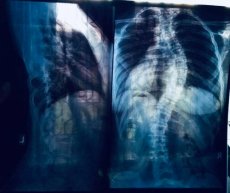

Під час звичайного профогляду в квітні цього року в сільській амбулаторії фельдшер звернув увагу, що хребет дівчинки надзвичайно швидко викривився. Через декілька місяців красуню Альону скрутило до сколіозу IV ступеню.

Допомогти дитині беруться лише в Київському ОХМАТДИТі. Заплановано термінову операцію для вживлення імплантів, які вирівняють дівчинці хребет. Хірурги чекають Альону 27 листопада в Києві.